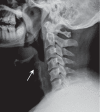

An epiglottic abscess is a rare complication of acute epiglottitis and is life threatening. We describe a case report of a diabetic adult male, who presented with an epiglottic abscess. Culture results showed Aeromonas hydrophila, an organism rarely reported as a cause of acute epiglottitis. Early recognition can be lifesaving.